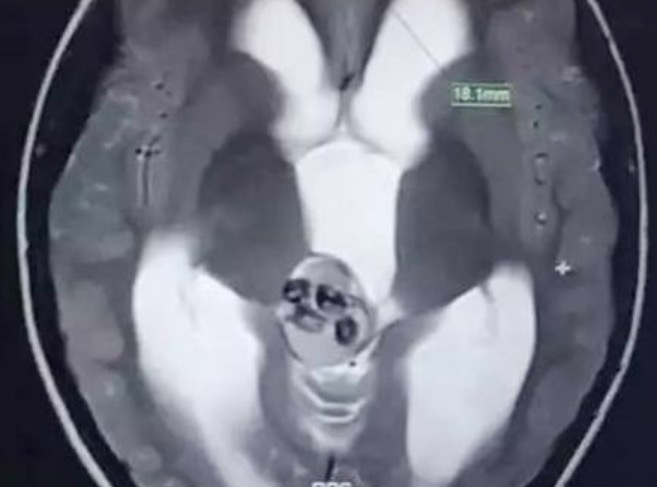

Um menino de 5 anos precisou passar por uma cirurgia no cérebro após um tumor chamado Teratoma, que não havia sido detectado desde o nascimento, começar a desenvolver dentes.

Conforme o jornal britânico "Mirror", os tumor foi descoberto quando a criança foi levada ao hospital após cair, vomitar e reclamar de fortes dores de cabeça.

A cirurgia foi feita no Hospital Infantil da Universidade de Medicina de Zhejiang (China). "O cérebro humano é delicado como um tofu, ainda mais o de uma criança. Foi como retirar ossos de um ovo cru. Foi uma cirurgia muito complicada", afirmou o cirurgião responsável pelo caso, Shen Zhipeng.